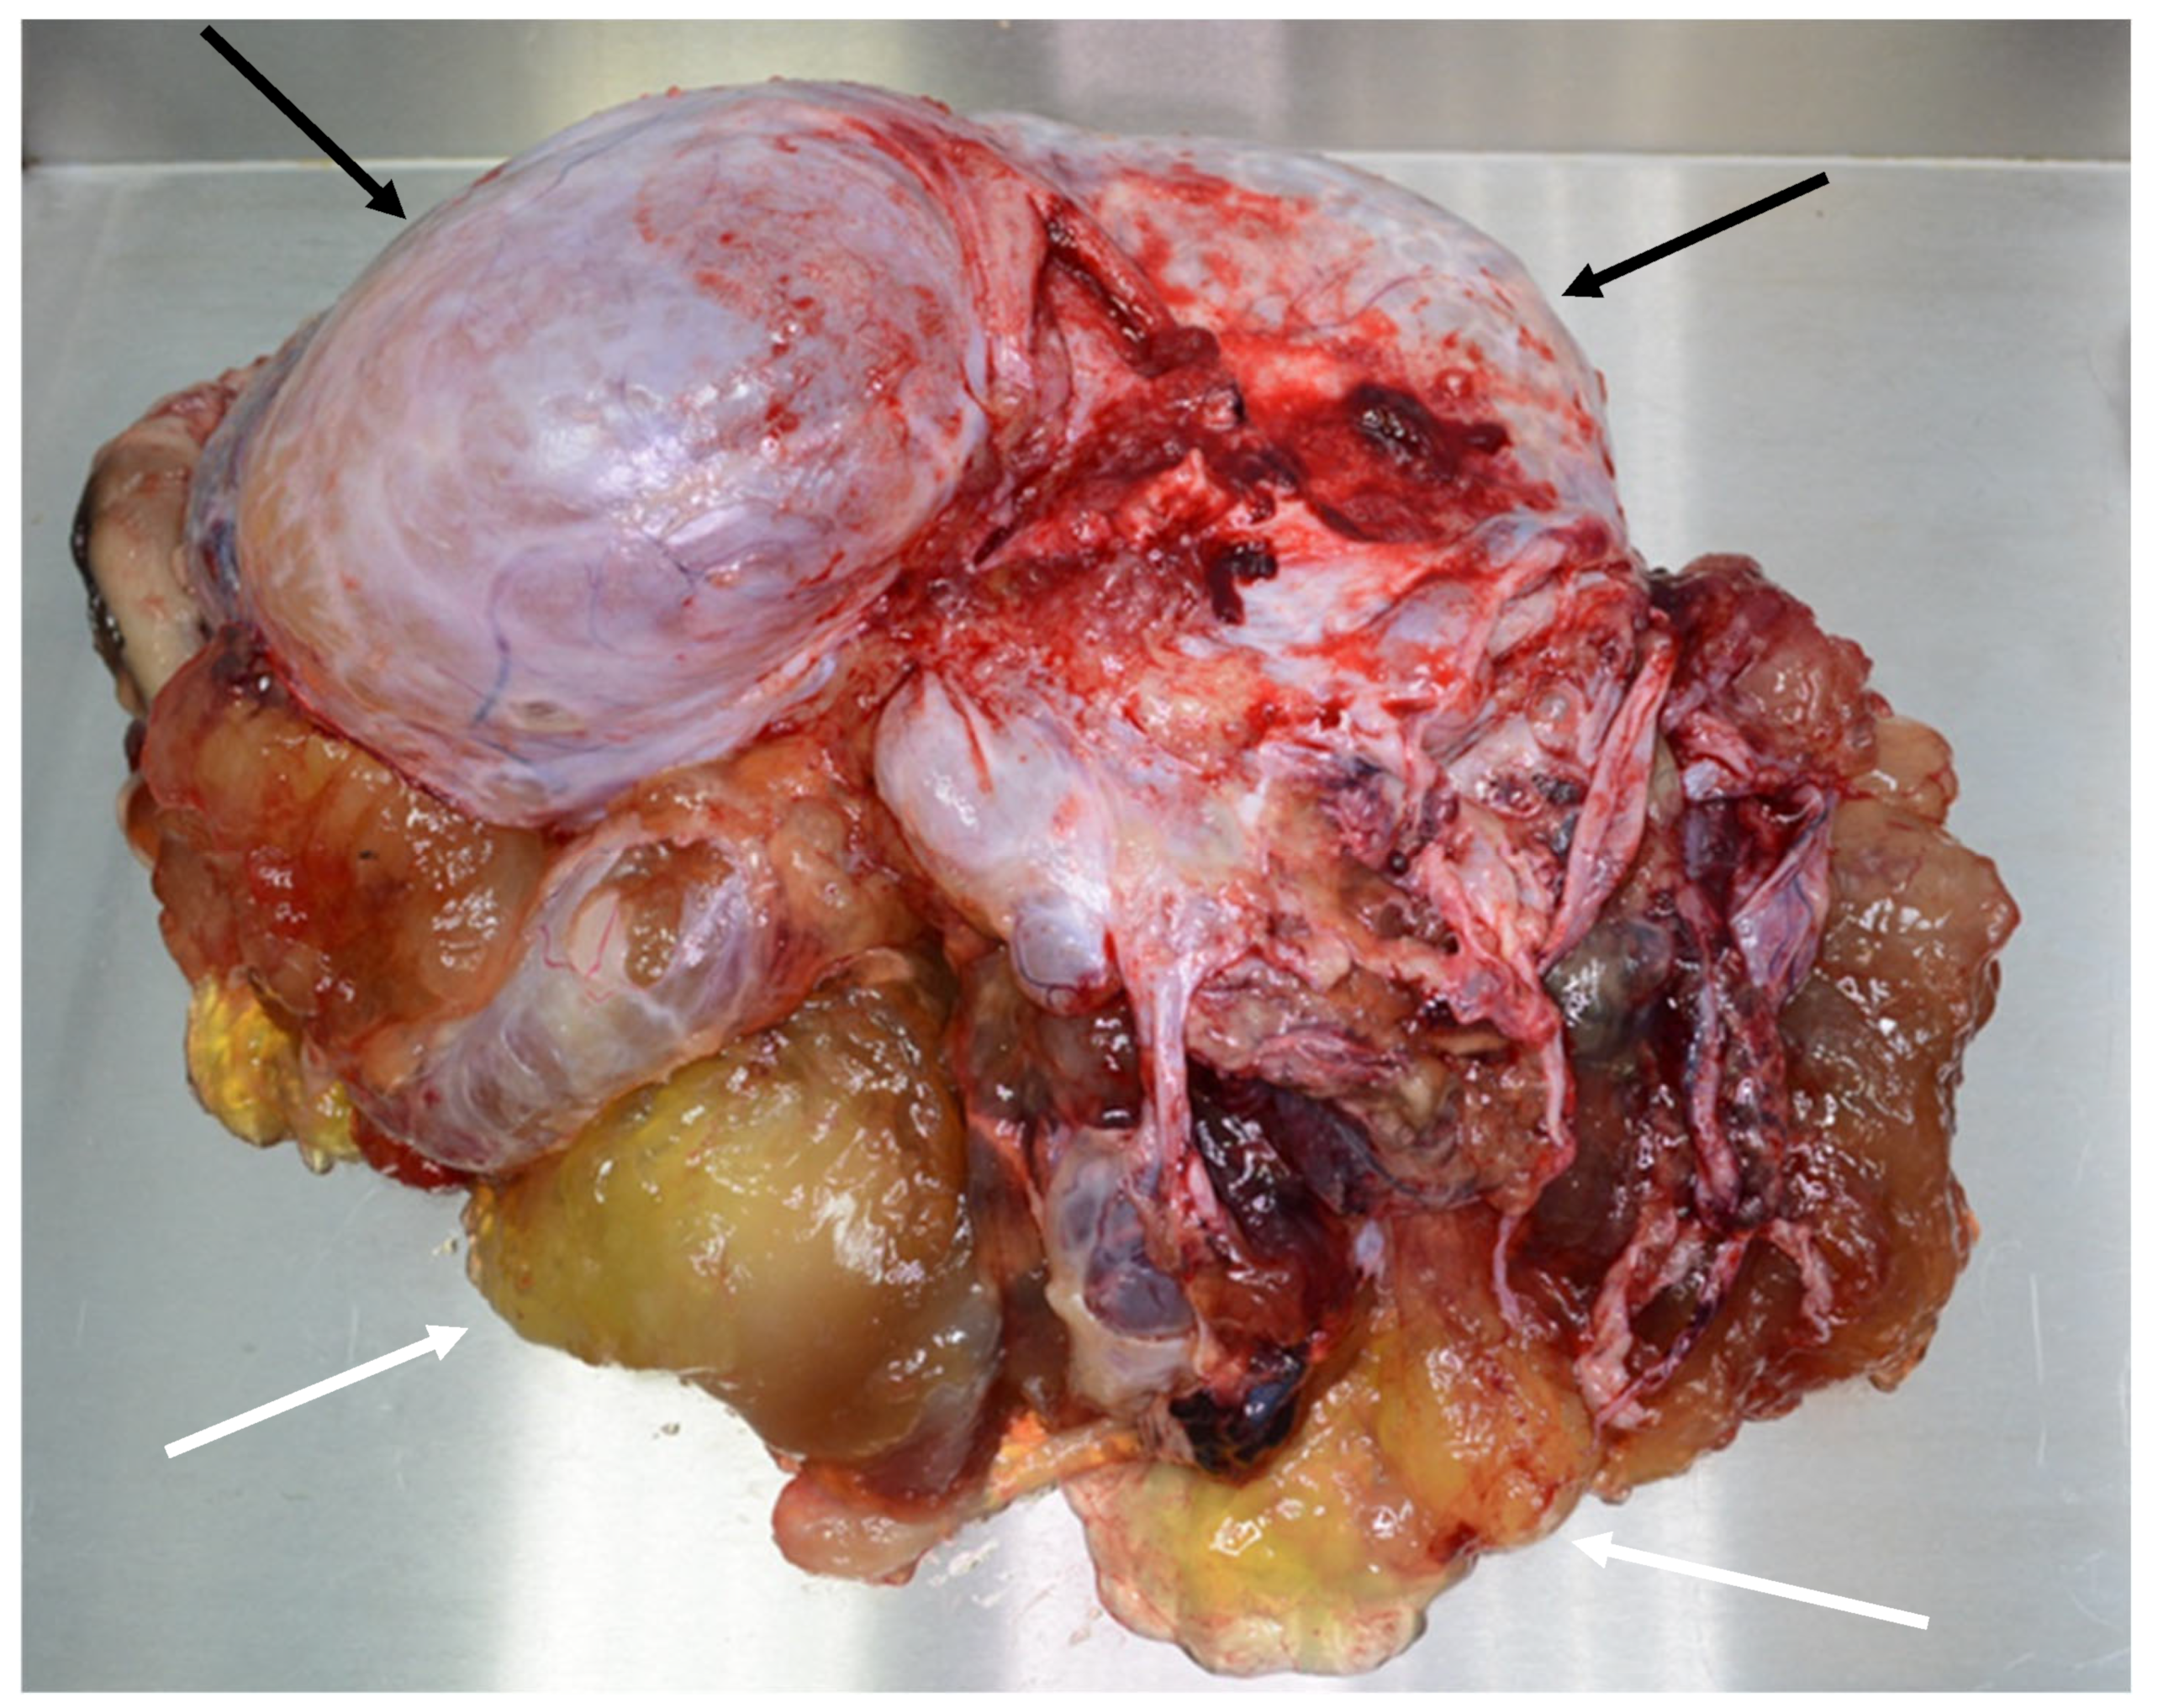

Figure 18. Specimen with tumor (black arrows) and mucin (white arrows).

Treatment of the advanced disease consists of maximal cytoreduction (Figure 18 and Figure 19), which means the removal of all visible tumors and HIPEC. The abdominal cavity is lavaged with a warmed cytostatic solution at 42 degrees Celsius for 90 min. The most commonly used cytostatic is mitomycin. The clinical classification of pseudomyxoma peritonei is based on the Sugarbaker peritoneal cancer index, which can stratify the extent of the disease. The radicality of surgery is assessed according to the cytoreduction score [3,8,12].